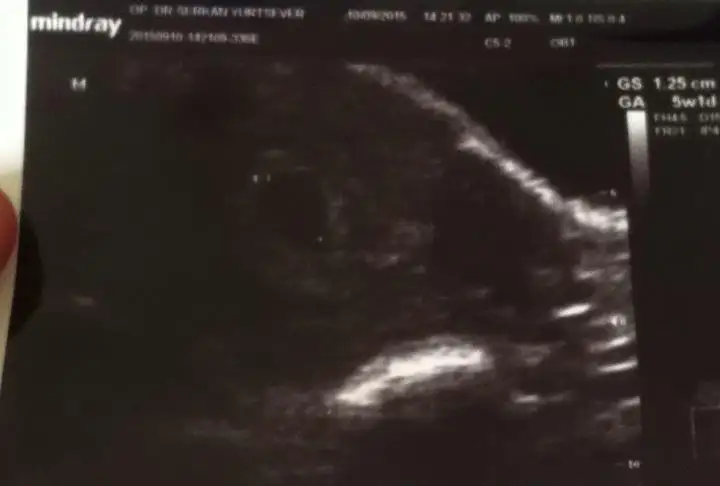

aynı durum ve korku bende de var 5+1 kese var hatta kesem 4 haftalıkken göründü 4 mm di dün 12 mm olmuş ama bebiş yok henüz daha erken dedi doktor ama insan endişeniyor işte boş gebelik korkusu bende de cok :KK43: Allah ım inş. öyle bişi olmaz sağlıklı sıhhatli kalp atışlarını duyar sonrada kucagımıza alırız bebişlerimizi

kese göründü . baska sehırde ogredım. orda dr gıttım 4 haftalık dedı tabı muhtemel sata gore konustu. şimdi izmire dondum burda kalp atışı için gittim ama malesef kese var bebek yok. dr 4 haftalık keseye gore dedı.:110::110::110:

canım benim 5+1 de bebiş görünmedi henüz 4 de görünmemesi bana görecok normal artık mecbur bekliycez birdaha nezaman gel dedi sana ? benim kese görüntüleri bak hiçbişi yok şimdilik daha :)

çok sağol inşallah geçer. benim 7+2 hamile diyor kese en son bu salı gittim 1.77 cm o boş gebelik lafını duydum ya kaç haftalık ne zaman doğum olur hiç bir şey sormadım güya kalp atışını duyacaktım.

ben deaşırı gaz olduğu için karından hiç göremedik hep alttan oldu kontrol dr. demedi 7 haftalık diye doğrusu ilk gittiğimde 28 agsts dr. 3 4 haftalık dedi en son 8 eylül yanı bu hafta gittim boş dedi iki dr. da hfta sormak aklıma gelemdi ilk dr erken bir zaman olduğu için net söylemedi ne biliyim

Salı günü doktora gittim ultrasonla baktı ve kalp atışı gördüğünü söyledi. Bebeğim 3.5 mm. Şu an için sağlıklı dedi.